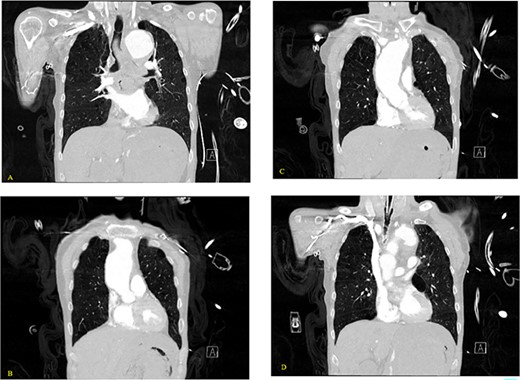

(A) Coronal and (B) sagittal views of the arterial phase CT chest with IV contrast performed during the initial trauma evaluation show aneurysmal dilation of the thoracic aorta with contrast extravasation into the esophagus and stomach.

(A–D) Coronal CT chest with contrast reveal the descending aortic aneurysm of at least 6.5-cm diameter. Deep ulceration in the descending aorta at approximately the level of the pulmonary artery bifurcation. The ulceration has eroded into the esophagus. Extravasation of contrast is observed from the ulceration into the esophagus.